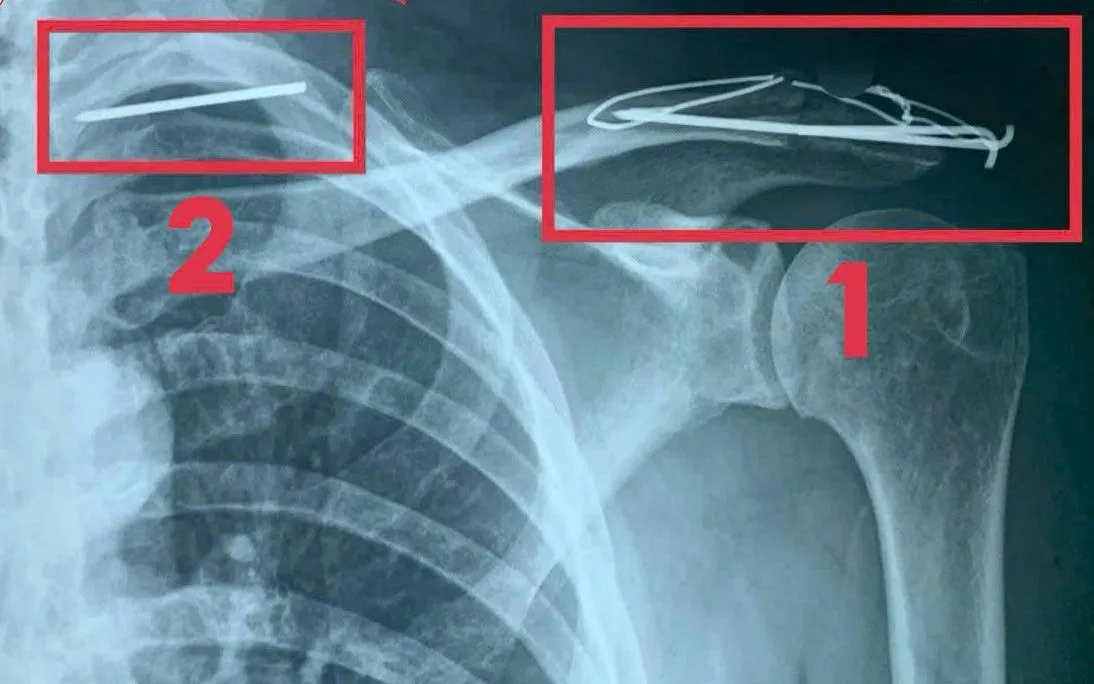

VTV.vn - Nam bệnh nhân 60 tuổi ở Quảng Trị bị gãy đinh Kirschner, di trú vào phổi trái sau phẫu thuật vai 3 năm trước, suýt nguy hiểm tính mạng.

Người bệnh đến viện để rút dụng cụ kết hợp xương sau phẫu thuật. Kết quả chụp CT ngực cho thấy một dị vật kim loại đã xuyên qua thành ngực, đi vào thùy đỉnh phổi trái và tiến sát cột sống cổ. Dị vật có nguy cơ di chuyển vào trung thất, gây tổn thương tim, phổi, mạch máu lớn - đe dọa tính mạng.

Khai thác bệnh sử, bệnh nhân cho biết từng phẫu thuật cố định trật khớp cùng - đòn bằng đinh Kirschner cách đây 3 năm. Tuy nhiên, ông không tái khám và tháo đinh đúng thời điểm (6-12 tháng). Hậu quả, đinh bị gãy và di trú vào trong lồng ngực.